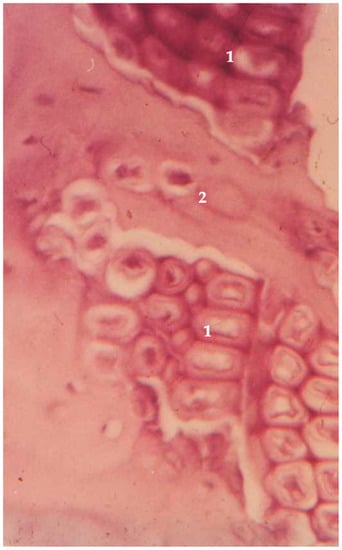

2. Similarities between Wood and Bone